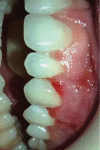

Gingival recession is an oral health problem that affects a large part of the population. Several treatments are suggested in the current literature; among them is the use of buccal fat pad grafting. The objective of this case report is to describe the treatment of a Miller Class I gingival recession using a nonpedicled buccal fat pad graft immediately after performing the surgery for buccal fat pad removal (bichectomy technique). First, bilateral surgical removal of the buccal fat pad was performed with the main objective of eliminating oral mucosa biting. The recipient site was prepared to receive a portion of the fat pad that was cut and macerated in a size that was sufficient to cover the recession. The patient was followed up at 15, 30, 60, and 365 days postsurgery, and the results showed an elimination of the oral mucosa biting and complete coverage of the gingival recession. It was concluded that the nonpedicled buccal fat pad graft is another option for the treatment of Miller Class I recessions.